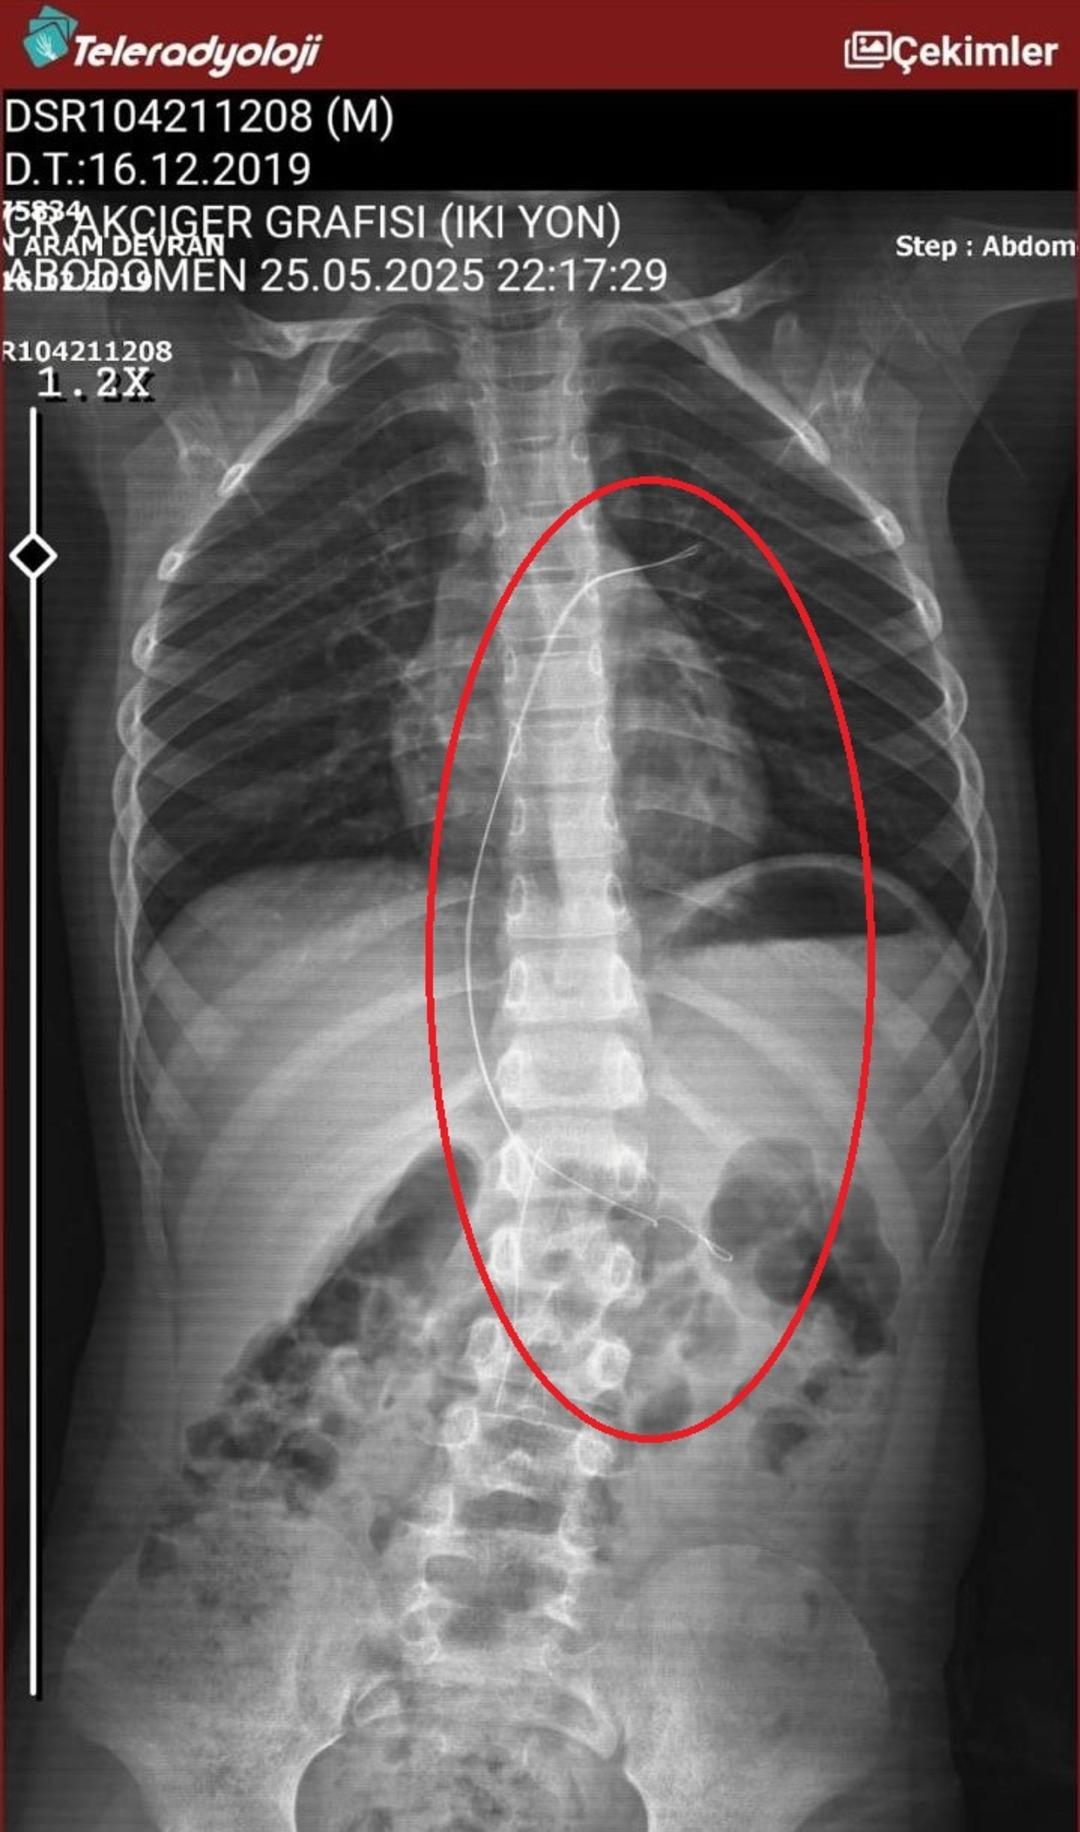

Seamore (37) ve Şaç’ta yaşayan Mehmet Ötün (40), Mayıs ayında bir parça salatalık yuttuktan sonra öksürük ve kusma şikayetleri gözlendiğinde Sernak Eyalet Hastanesine getirildi. Burada, ARAM gövdesinde yarıçap X ve manyetik rezonans görüntüleme unutuldu. Diyarbakir Gazi Yeşargil’in eğitim ve araştırma hastanesi jinekolojiye ve ARAM’lar için ek binaya yönlendirildi, 18 santimetrede 5.5 saatlik riskli cerrahi kaldırıldı. Postoperatif araştırmalarda, kateter kalp kapakına ve karaciğere zarar vermeye kararlıydı.